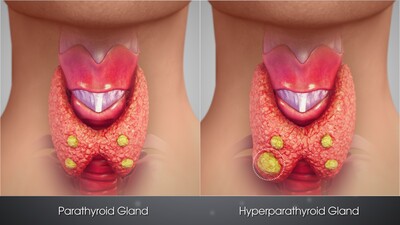

МОЧЕКАМЕННАЯ БОЛЕЗНЬ

Информационный раздел по МКБ